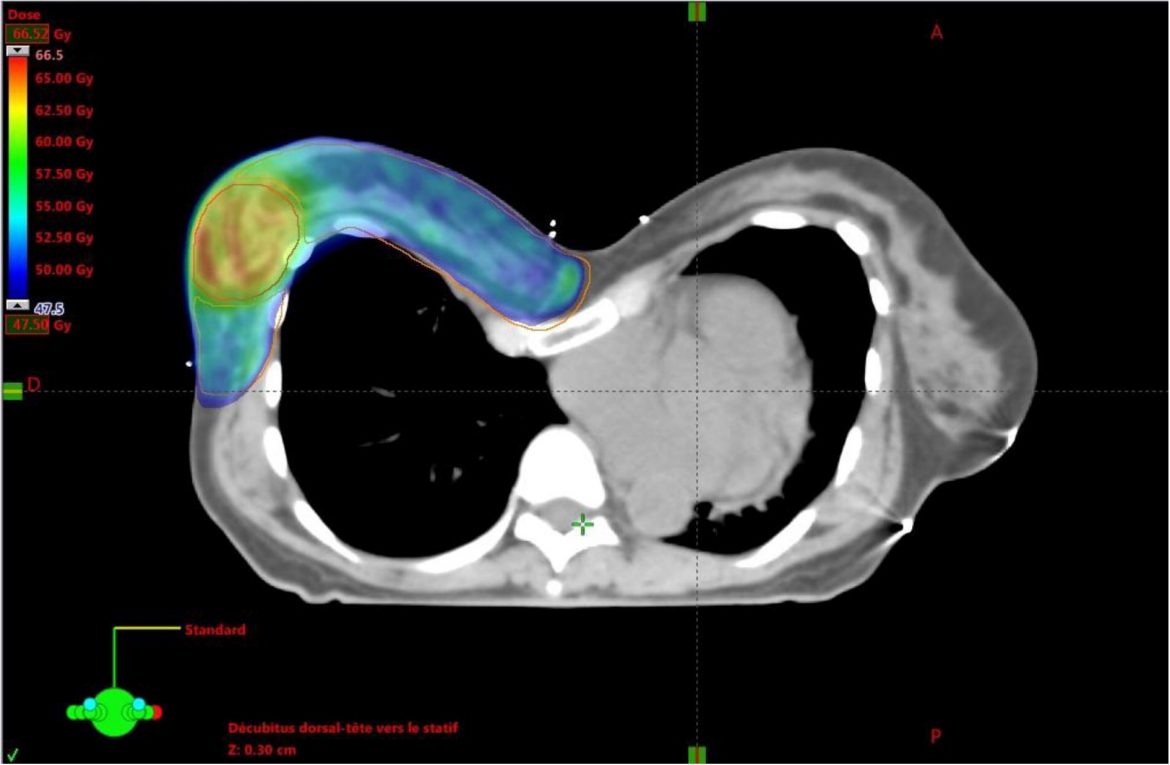

– Xạ trị vùng hạch thượng đòn có thể dẫn đến tăng thể tích nhu mô phổi nằm trong trường chiếu xạ, do đó, cần chú ý đến giới hạn liều cho phổi cùng bên (ngưỡng V20 dưới 30% được chấp nhận rộng rãi trên thực hành lâm sàng).

– Rất khó để có thể chỉ ra những phân nhóm bệnh nhân cụ thể nào sẽ nhận được lợi ích từ xạ trị hạch vú trong. Quyết định chỉ định xạ trị cần xét đến tổng hoà các yếu tố dự báo nguy cơ di căn hạch vú trong bao gồm: Tình trạng di căn hạch nách, khối u vú (vị trí, giai đoạn T), tuổi bệnh nhân.- Khi thực hiện xạ trị hạch vú trong, nguy cơ độc tính đến tim cần được đặc biệt chú ý. Thông số được xem là tốt nhất để đánh giá là liều xạ trung bình tại tim, không nên vượt quá 5 Gy. Bên cạnh đó, những điều trị phối hợp có thể ảnh hưởng đến tim (hoá trị, trastuzumab…) cũng như tình trạng bệnh lý tim mạch kèm theo của bệnh nhân cần được tính đến. Với những bệnh nhân có sử dụng Trastuzumab, liều xạ trung bình tại tim không nên vượt quá 3 Gy.